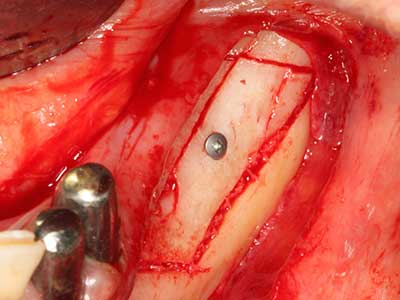

Fig. 18: Preparación de una tapa cortical con la sierra ósea piezoeléctrica (Piezomed, W&H).

Fig. 19: Zona operada después de neurolisis y eliminación del osteomo.

Fig. 20: La tapa ósea extraída se readapta y se fija mediante un tornillo para osteosíntesis (KLS Martin, Tuttlingen).